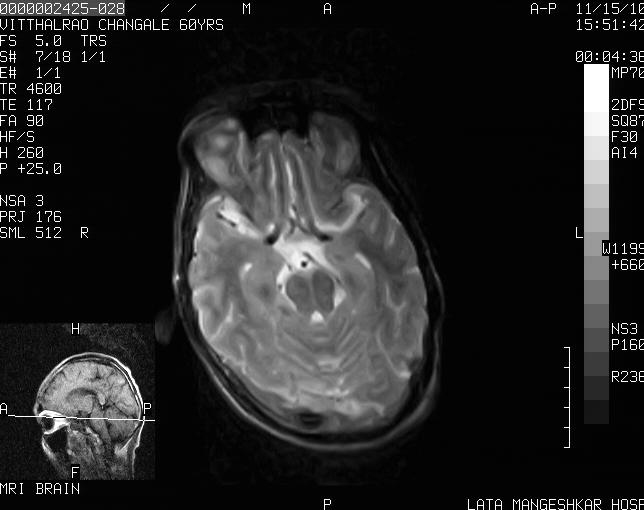

Fig 5: Shows MRI BRAIN (plain) - with edematous 7th and 8th nerve complex s/o inflammatory focus